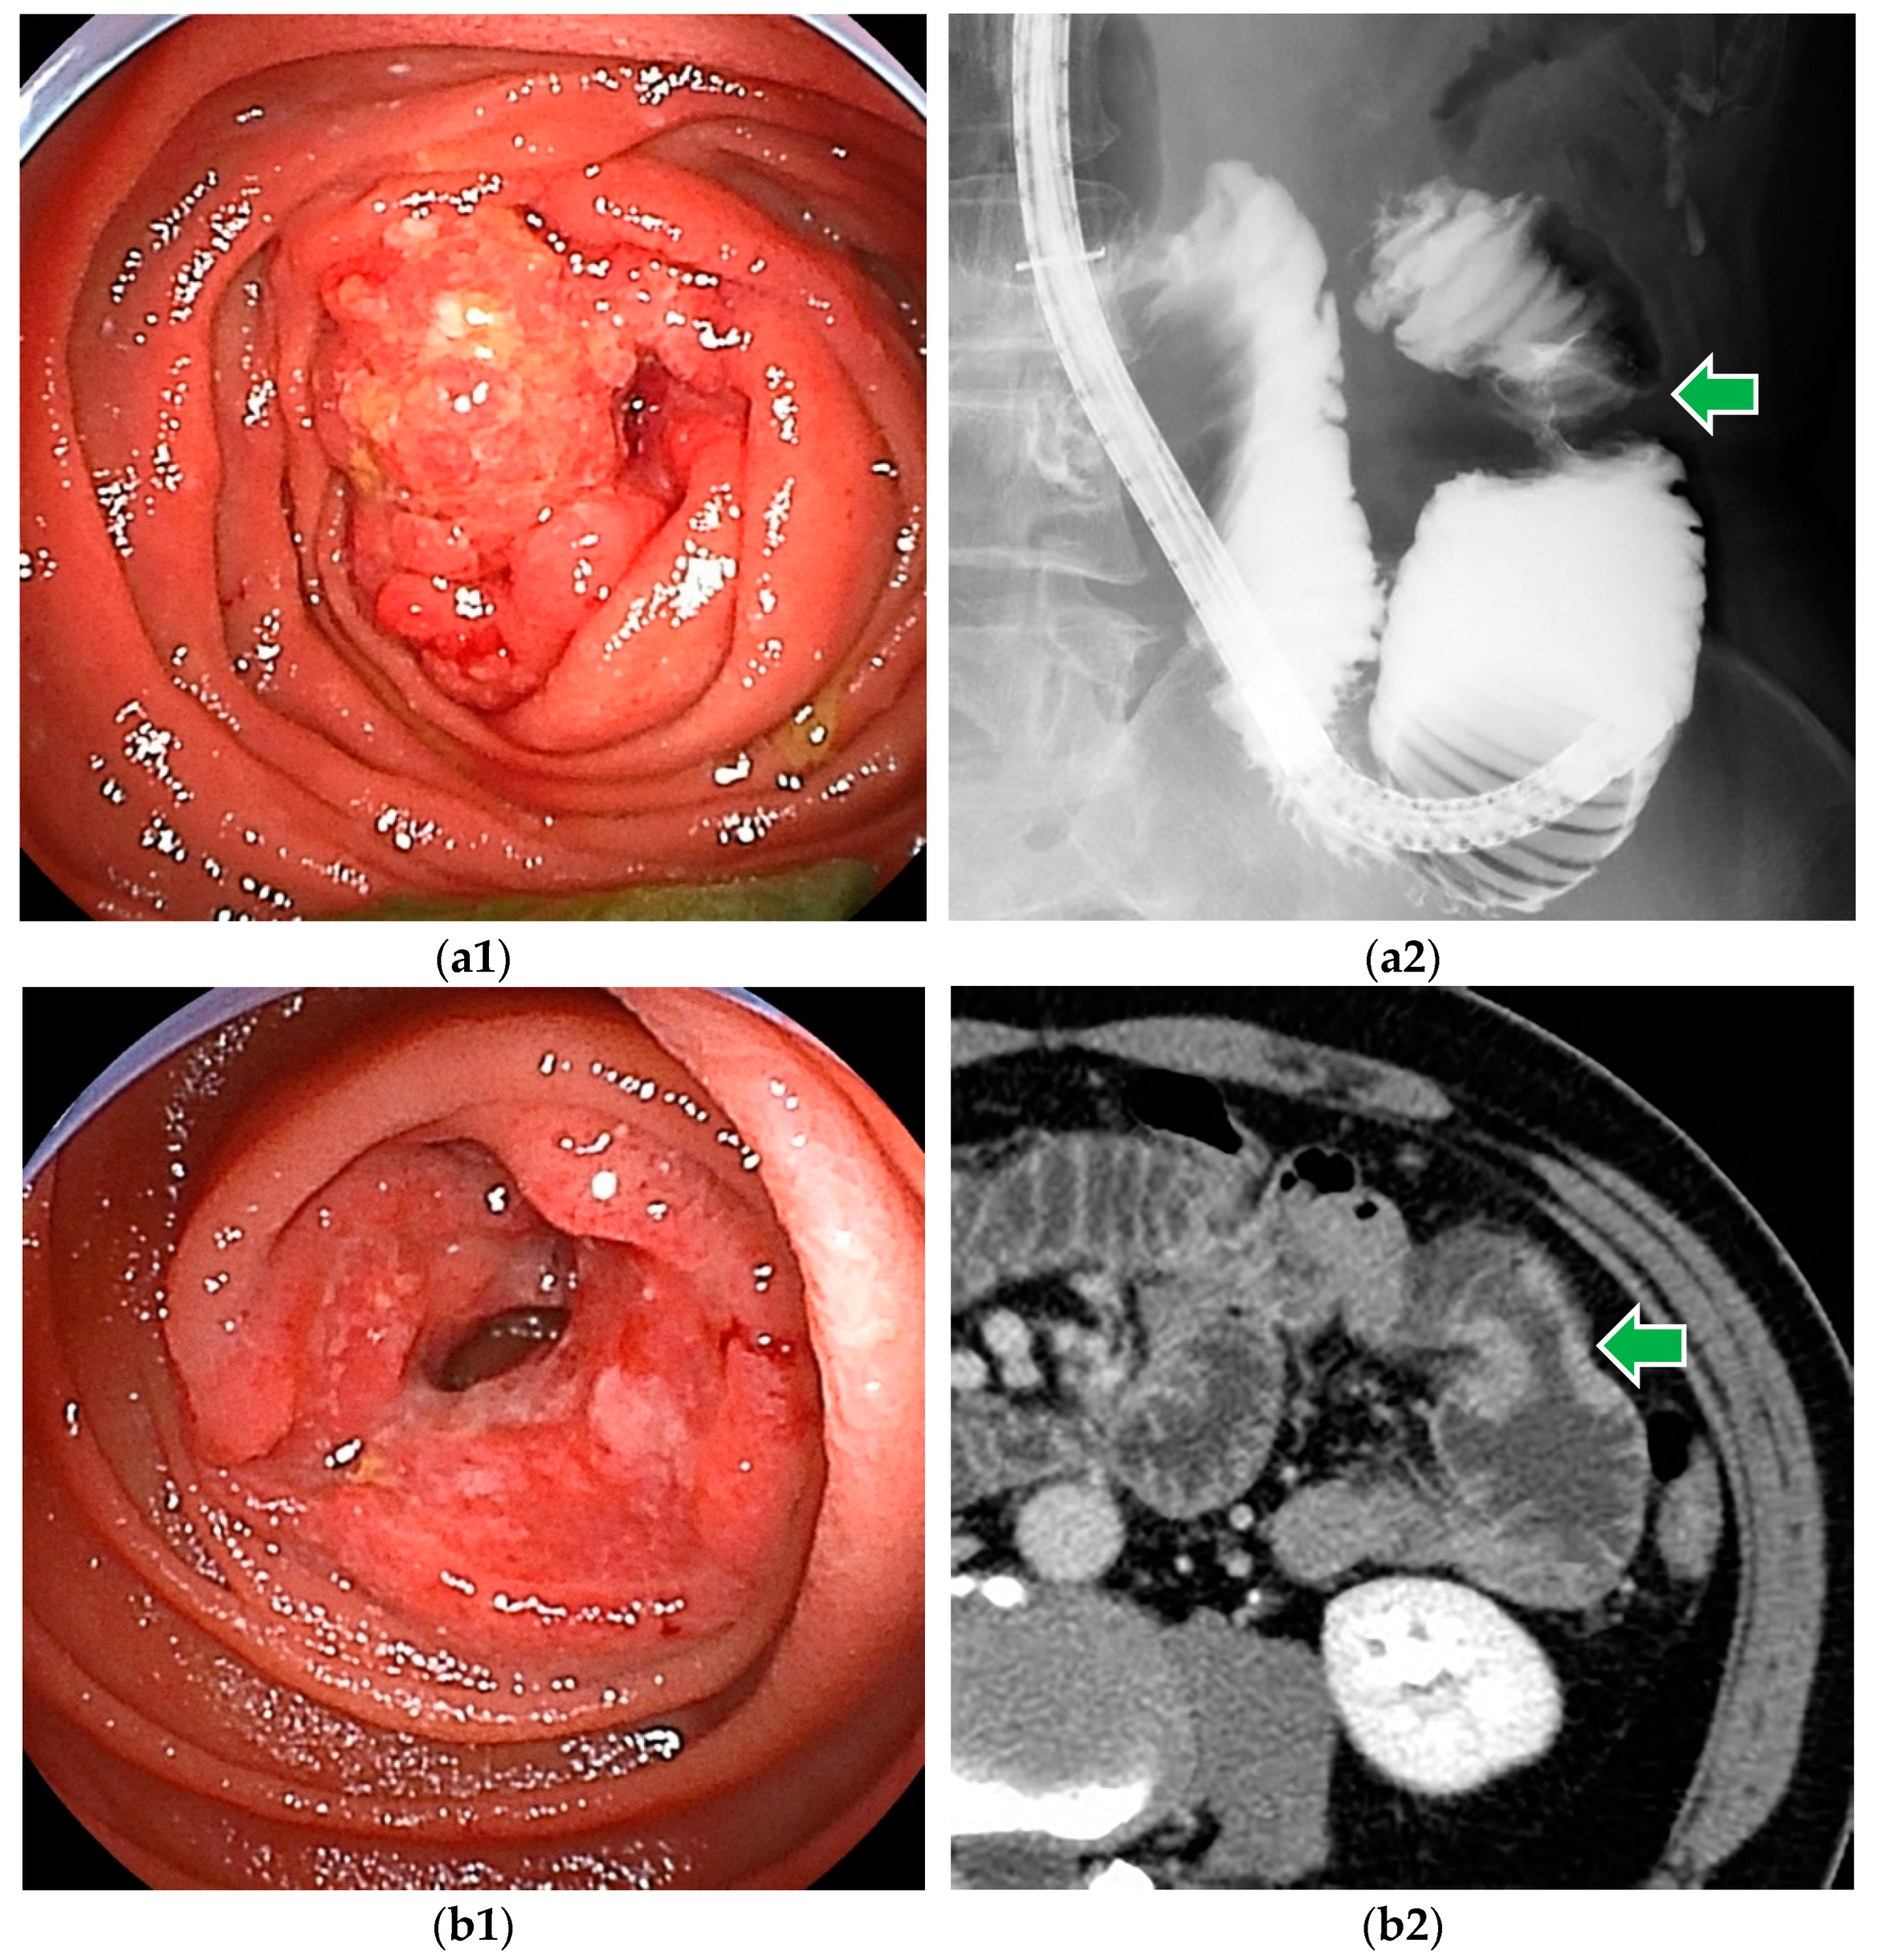

Figure 1.

Small bowel adenocarcinomas, which are often advanced at the time of diagnosis, and endoscopic findings often include ulceration and stenosis. (a1,a2) DBE revealed adenocarcinoma in the proximal jejunum. Endoscopic enteroclysis showed the stenosis as an apple core sign. (b1,b2) DBE revealed adenocarcinoma with ulceration. CT showed mild stenosis.

BAE, or push enteroscopy, can reach the lesion (Figure 1), take a biopsy for histopathologic diagnosis, and mark it by tattooing for surgical treatment. Endoscopic findings of small bowel adenocarcinoma often include ulceration and stenosis. Type 2 (54.2%) was the most common among the macroscopic types, followed by Type 3 (18.2%) [5].